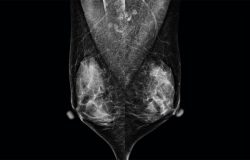

Mejorando la Experiencia de Imágenes Mamarias con un Rendimiento Premium, Potente y Continuo en Imágenes Diagnósticas.

- Sistema de mamografía digital de alto rendimiento.

- El tamaño de píxel más pequeño: 65um.

- Tecnología de alta definición.

- Visualización nítida de microcalcificaciones en imágenes mamarias.